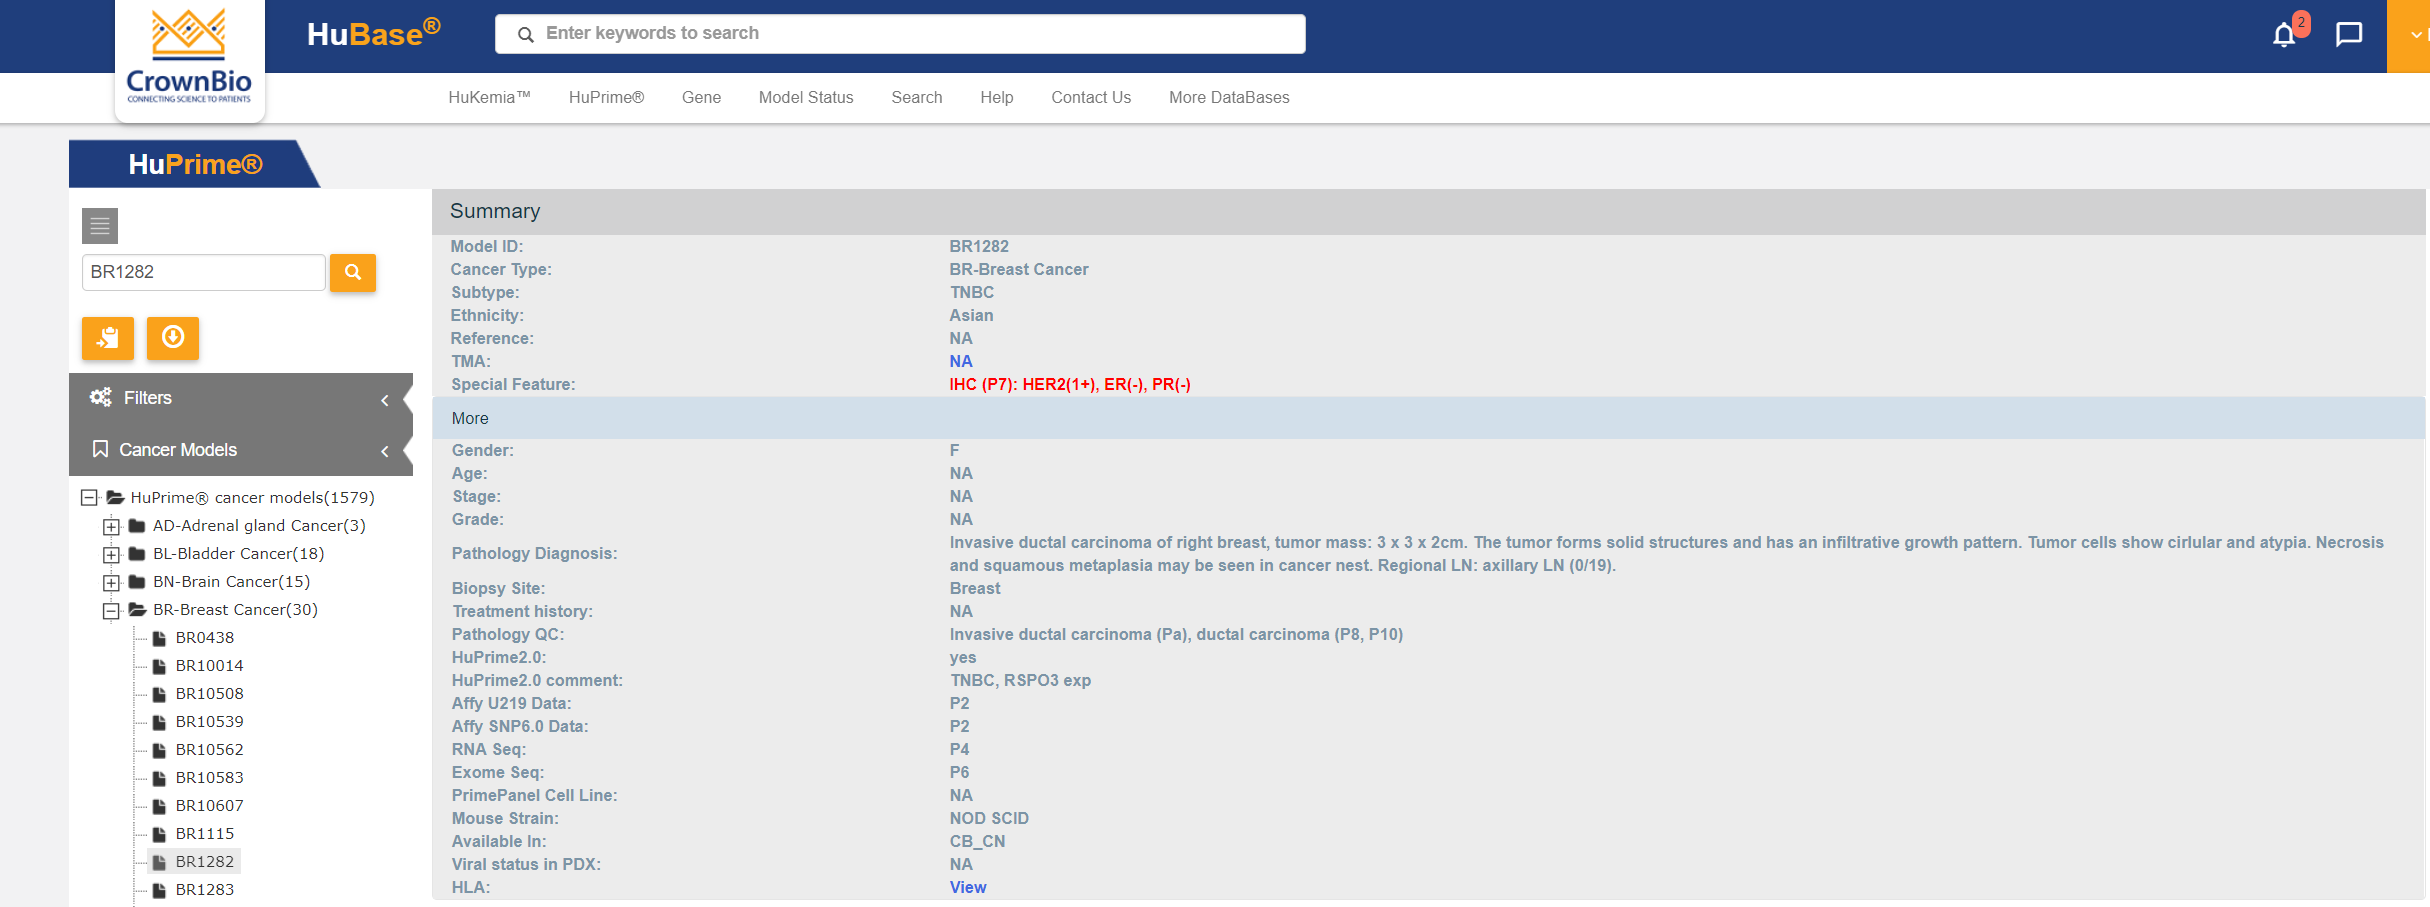

可搜索PDX模型数据库HuBase™中的大量特性鉴定数据包括:超过1,500个模型的RNAseq、超过680个模型的全外显子组测序、组织学、生长动力学以及SoC和研究性治疗数据。

登录并在我们可搜索的数据库内探索冠科生物具备完善表征的人源肿瘤异体移植模型。获取基因组、分子和表现型数据,包括肿瘤生长曲线、标准治疗反应、组织病理学数据的患者信息

浏览或搜索我们的模型库从而获取患者信息和模型特定特征。